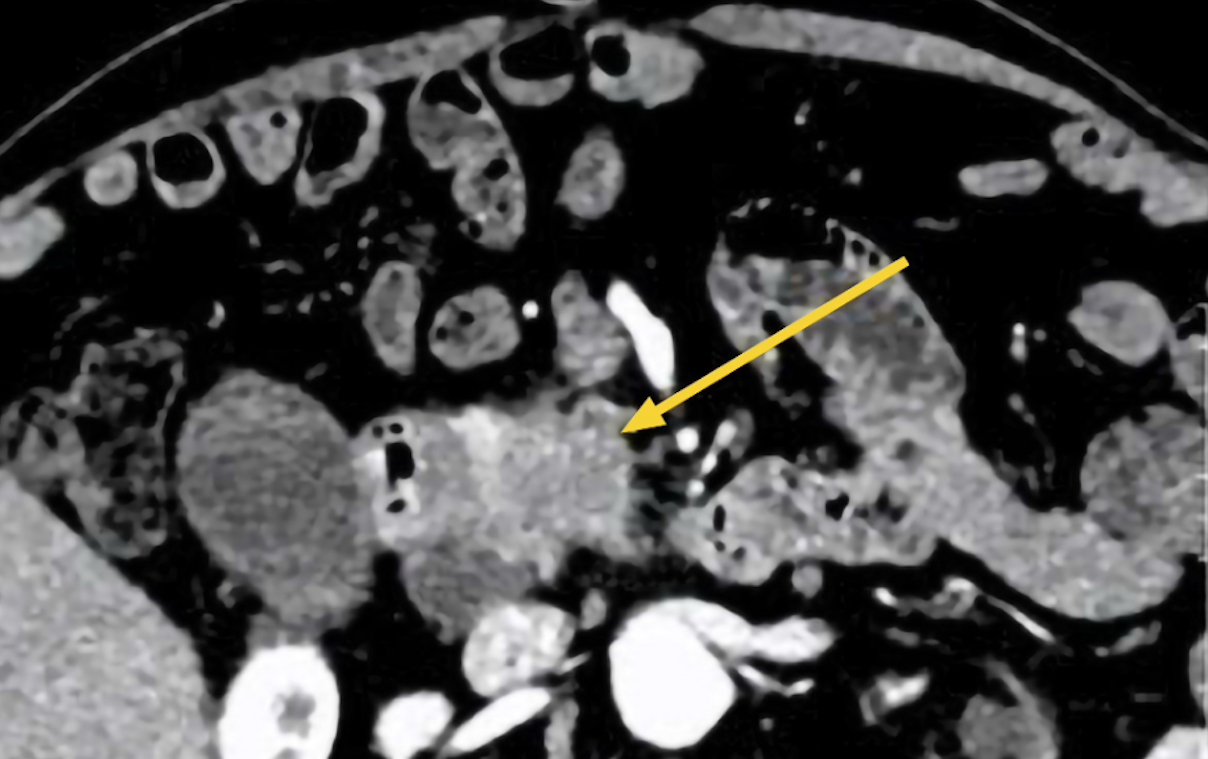

An abdominal ultrasound revealed a hypoechoic mass measuring approximately 70 mm in the head of the pancreas, accompanied by surrounding tissue edema. Smaller lesions were also noted in the body and tail of the pancreas. A subsequent abdominal CT scan confirmed a lesion in the pancreatic head, causing dilation of both intrahepatic and extrahepatic bile ducts, leading doctors to suspect malignancy. The tumor had indistinct margins with the D2 segment of the duodenum. The gallbladder was distended and contained gallstones and biliary sludge, with several lymph nodes observed around the pancreatic head and porta hepatis.

CT scan showing Mr. Hung's pancreatic head lesion (yellow arrow). *Photo: Tam Anh General Hospital* |